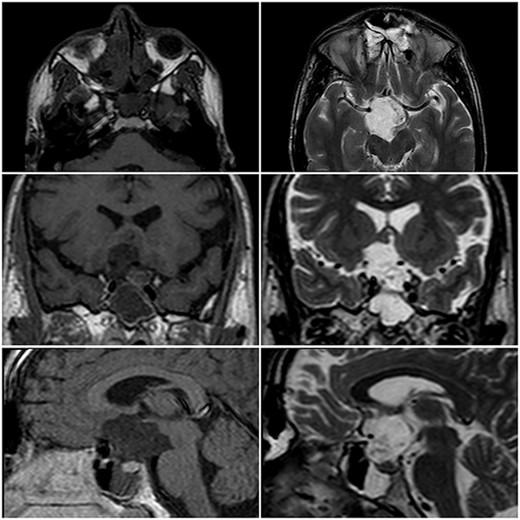

A 22-year-old caucasian male was admitted to neurosurgery department with a history of chronic headache and 8-month history of bilateral visual acuity deterioration. Ophthalmologic evaluation revealed light perception on the right side and hand motion on the left side. Fundus examination showed bilateral temporal optic nerve pallor. Eye movement was normal. The patient had no focal neurological deficits. Laboratory tests were unremarkable. Magnetic resonance imaging (MRI) revealed a sellar and suprasellar well-defined cystic lesion with irregular margins, measures about 2.6 × 3.3 × 4 cm. The mass was hypointense in T1-weighted images (T1WI) and hyperintense in T2-weighted images (T2WI) with restriction in diffusion-weighted images (DWI). The mass was compressing the optic chiasm and surrounding the right optic nerve and pituitary stalk (Fig. 1). The patient underwent an endoscopic surgery and transnasal trans-sphenoidal approach was used to resect the cyst. A drilling of the sphenoid sinus septations was done. Using the Kerrison, the superior half of the posterior bony wall of the sphenoid sinus was removed to reach the sellar and suprasellar region. The dura was incised widely. We observed a sac within the sella compressing the pituitary gland. The sac was extended to the suprasellar region compressing the optic chiasm and reached to the floor of the frontal lobe anteriorly. The sac was opened and completely evacuated of cheesy materials. After evacuation of the cyst, we detached the epidermoid capsule from the pituitary gland and displaced the sac upward into the suprasellar region. A smooth dissection was applied to detach the capsule of epidermoid from the optic chiasm down to the posterior frontal lobe. We used a bipolar diathermy to coagulate small bleeding vessels. A 30° endoscope was used to confirm a complete resection of the sac (Fig. 2). An underlay graft from fascia lata of musculus quadriceps femoris was used to cover the defect of skull base and reinforced with fat tissue, nasoseptal flap and thrombin-soaked collagen sponges. Pathology revealed sheets of keratin indicating an EC (Fig. 3). Two days after surgery, the patient experienced sudden onset of high-grade fever and neck stiffness. The CSF opening pressure was normal and cultures for bacteria, mycobacteria and fungi were negative. The cell count and glucose and protein levels were normal. Based on the CSF findings, a diagnosis of aseptic meningitis was established. Conservative management was applied and the meningitis was resolved. Seven days after surgery, the patient showed partial recovery in visual acuity of the left eye with no improvement on the right side. On 6-month follow-up, the patient remained stable and no complication was developed. Brain MRI demonstrated no evidence of residual or recurrent lesion.

MRI in axial, coronal and sagittal views. The lesion appears with hyposignal in T1WI and hypersignal in T2WI.